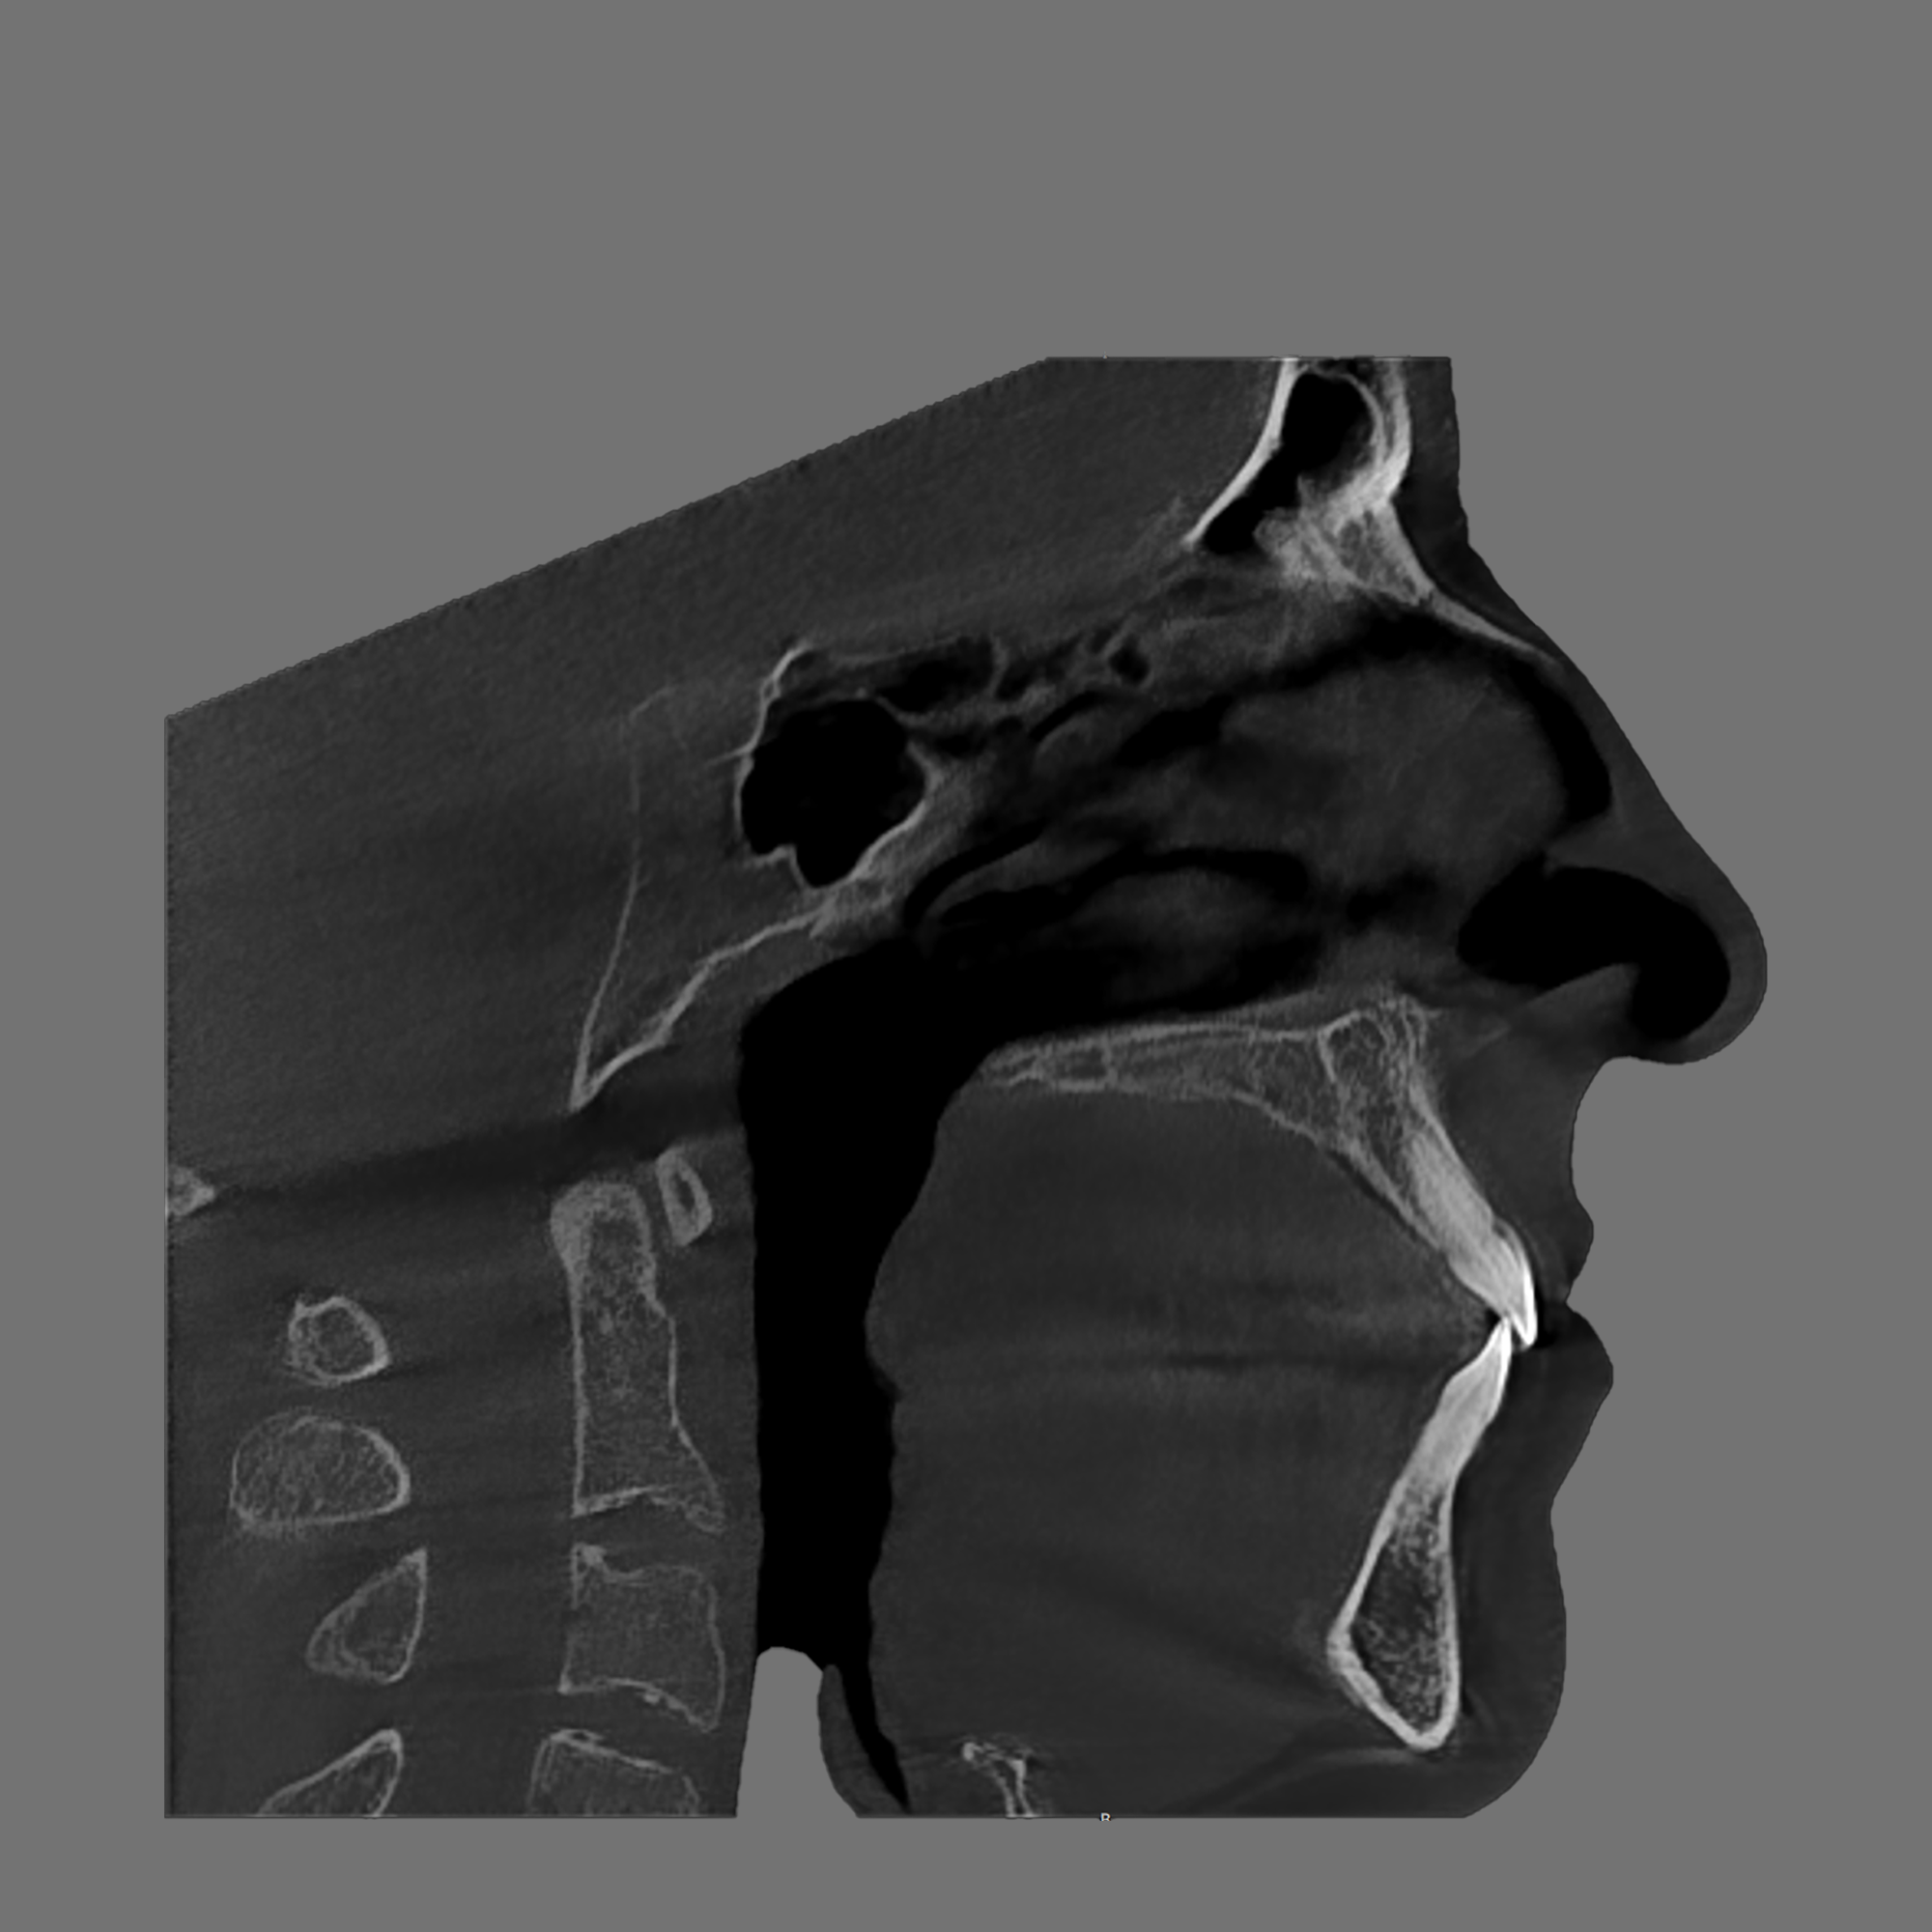

If you struggle with snoring, mouth breathing, poor sleep, fatigue, headaches, grinding, or focus issues, airway diagnostics can help identify root cause. It’s also valuable for children with crowded teeth, narrow arches, or sleep and behavior challenges.

Your evaluation includes a CT scan, comprehensive oral images, sleep assessment, and personalized treatment plan from Dr. Trivedi. If you choose to proceed with the complete solution stack, your evaluation costs will be applied as a discount.

After your evaluation, the doctor reviews your results and explains how your airway structures are impacting your health. You’ll then receive a personalized plan that may include palatal expansion, aligners, or other therapies to optimize your health.